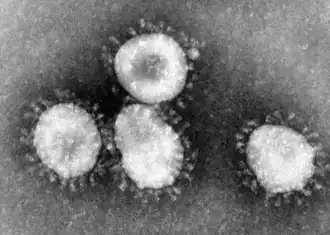

L'identification du virus a été assez rapide (quelques mois contre plusieurs années pour le VIH dans les années 1980), 11 laboratoires ayant été mobilisés par l'OMS. Le virus responsable du syndrome respiratoire aigu sévère, SARS-CoV, appartient à la famille des Coronaviridæ, au genre des Coronavirus.

Les coronavirus sont des virus enveloppés à ARN simple brin de polarité positive. En microscopie électronique, les particules virales présentent des protubérances de surface leur donnant un aspect « en couronne » (corona, en latin) qui a servi à la dénomination de ces virus. La classification en coronavirus résulte de tests de réaction sérologique et d'analyses des séquences génomiques. La famille des Coronaviridæ est divisée en trois groupes : le groupe 1 (coronavirus canin, coronavirus félin entérique FECV et de la péritonite infectieuse féline FIPV, virus de la gastroentérite transmissible du porc et virus respiratoires porcins), et le groupe 2 (coronavirus bovin, virus des hépatites murines, virus de la silodacryonite du rat et coronavirus humain OC43) comprennent les virus infectant des mammifères. Le groupe 3 est constitué de virus réputés exclusivement aviaires (virus de la bronchite infectieuse aviaire, coronavirus du dindon).